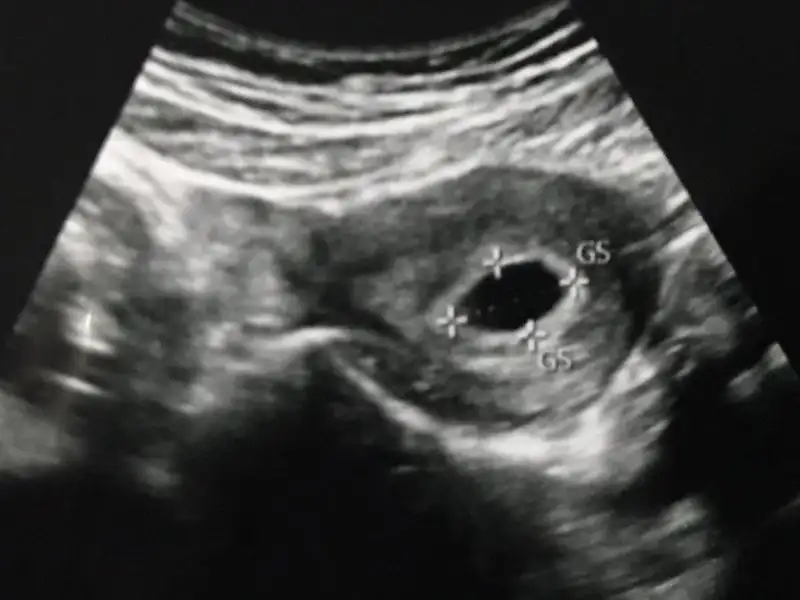

Eki Görüntüle 2065136

Embriyo görünmüştü cnm nokta halinde. Ultrason fotosunda çıkmamış ancak biz ekrandan hem yolku hem de emriyo yu görmüştük.

5+3 haftalik